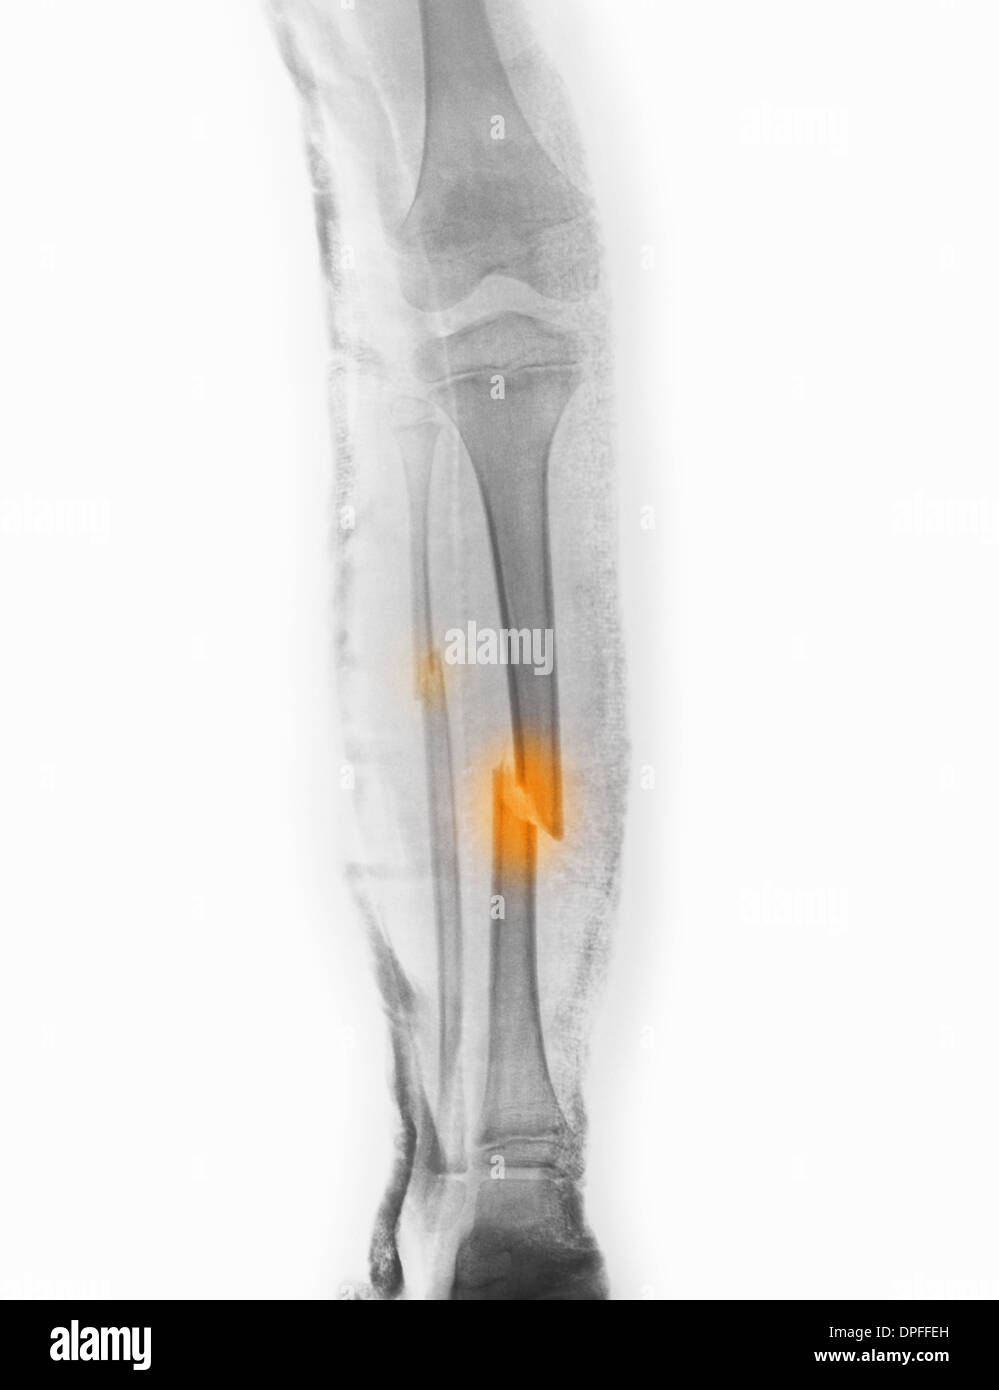

Gesso e paracetamolo come antidolorifico. Pubblicato in 16 august 2017. La frattura di tibia e perone, che nei casi più gravi diventa una frattura scomposta tibia e perone, è conseguente a forti traumi come per esempio accade cadendo con la moto, negli incidenti stradali e negli sport da contatto.

Un video con immagini della mia gamba sx dopo l'incidente in moto. La frattura di tibia e perone, che nei casi più gravi diventa una frattura scomposta tibia e perone, è conseguente a forti traumi come per esempio accade cadendo con la moto, negli incidenti stradali e negli sport da contatto. Fortunatamente l'uomo, un sessantenne del paese, rimasto schiacciato dall'albero, ha riportato solo una frattura alla gamba sinistra: 7° giorno frattura tibia perone 6° dopo operazione con perno/chiodo endomidollare tibia. Buonasera, lo scorso novembre ho riportato una frattura scomposta del iii distale di tibia e perone trattata con chiodo endomidollare e successivamente ho rimosso la vite statica in zona ginocchio. Esperto in assicurazioni , gestione sinistri e risarcimento danni. Volevamo sapere i tempi di guarigione , se deve fare le fisioterapie e se dopo la guarigione ritorni a camminare come una volta. Il giovane australiano ha riportato la fratture della tibia e del perone della gamba destra, ed è stato sottoposto a un intervento chirurgico per stabilizzare le due fratture con placche e viti di compressione. Il pesante tronco gli ha spezzato sia tibia che perone. Il dolore è fortissimo il dott mi ha dato targin 5 mg 2 volte al dì, alla prima pastiglia mi è venuta un emicrania fortissima, posso alternare con tachipirina 1000 così passa mal di testa e attenuo dolore gamba? Erano all'incirca le 10 di mercoledì, 26 marzo. 4 видео 330 просмотров обновлен 22 дек. Ciao , mia nonna ha subito una frattura scomposta alla tibia ed al perone. Nel maggio 2004 ho avuta la frattura scomposta di tibia e perone durante una partita di calcio. Il problema e' quello, pur facendo agonismo ho avuto due gravi infortuni propio fuori dalle gare, l'anno scorso a giugno sono stato investito in pieno da un auto in allenamento in una strada semi deserta e questa volta sono caduto da fermo su un tombino spezzandomi di netto tibia e perone. Pagina creata per la squadra di calcio a 5 iscritta al campionato csi di carpi. Come praticamente tutte le altre ossa del corpo umano, anche tibia e perone possono essere oggetto di frattura a seguito di traumi rilevanti a loro carico.